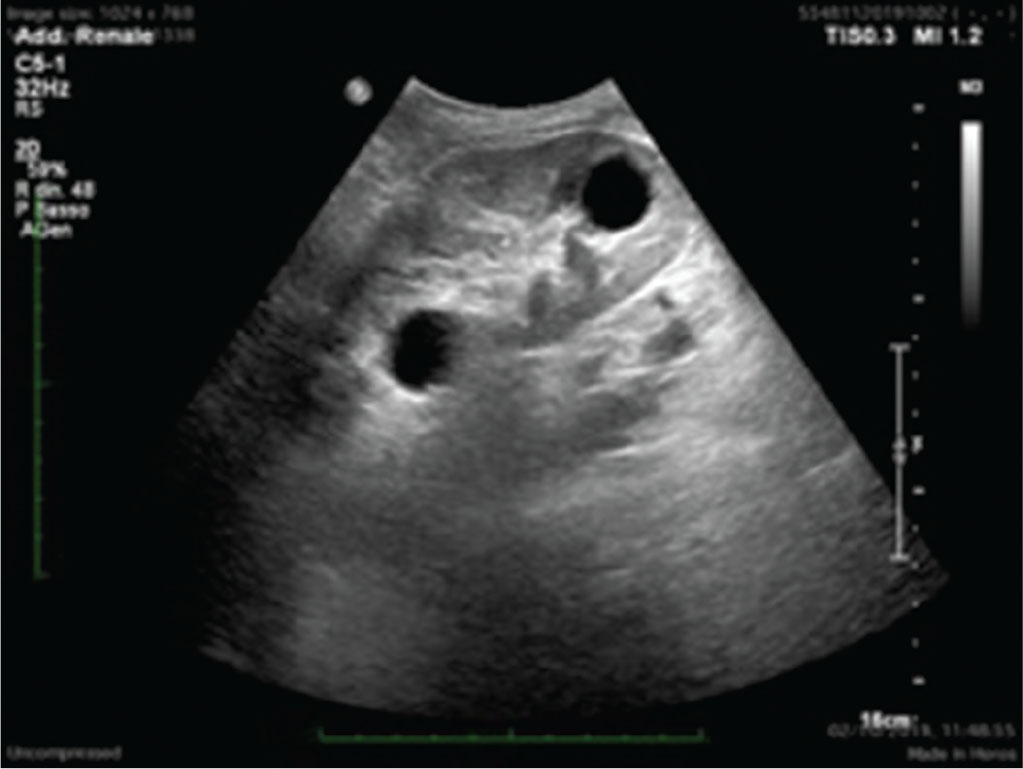

Il riscontro di cisti renali è, invece, molto frequente nel rene trapiantato (Fig. 5).

Le cisti, che vanno ben caratterizzate fin dai primi riscontri ecografici per attuarne, poi, un follow-up ecografico, possono essere già presenti nel rene al momento della donazione oppure possono formarsi negli anni successivi al trapianto. Queste cisti possono distribuirsi ubiquitariamente nel parenchima renale. È importante, in ogni caso, attuarne uno stretto monitoraggio per identificarne eventuali modifiche strutturali potenzialmente in senso neoplastico.

(Personal image, Fondazione IRCCS Ca’ Granda Ospedale Maggiore Policlinico, Milano)